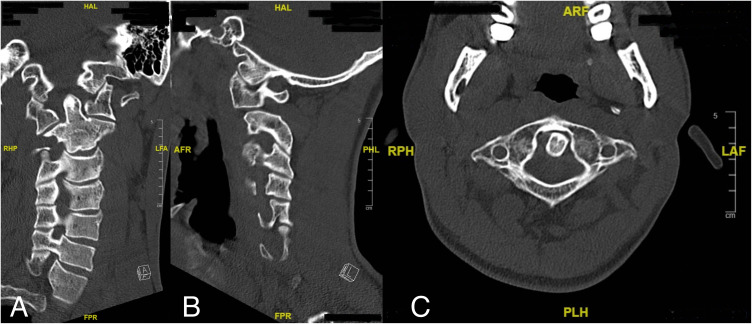

Introduction: Dystonia is a prevalent movement disorder characterized by involuntary muscle contractions, and cervical dystonia is among the most common forms. This report presents a rare case of severe isolated cervical dystonia in a young male patient that progressed to type IV atlantoaxial rotatory subluxation, highlighting the clinical presentation and diagnostic challenges associated with this condition.

Case description: A 27-year-old male patient presented with abnormal head posture and severe cervical pain. Clinical examinations revealed severe cervical muscle spasms and a unique head posture, as if he was looking at the tip of his right shoulder. Radiological evaluation revealed a type IV atlantoaxial rotatory subluxation. Despite initial attempt of close reduction under anesthesia, recurrence of the subluxation occurred, and surgical intervention was necessary.